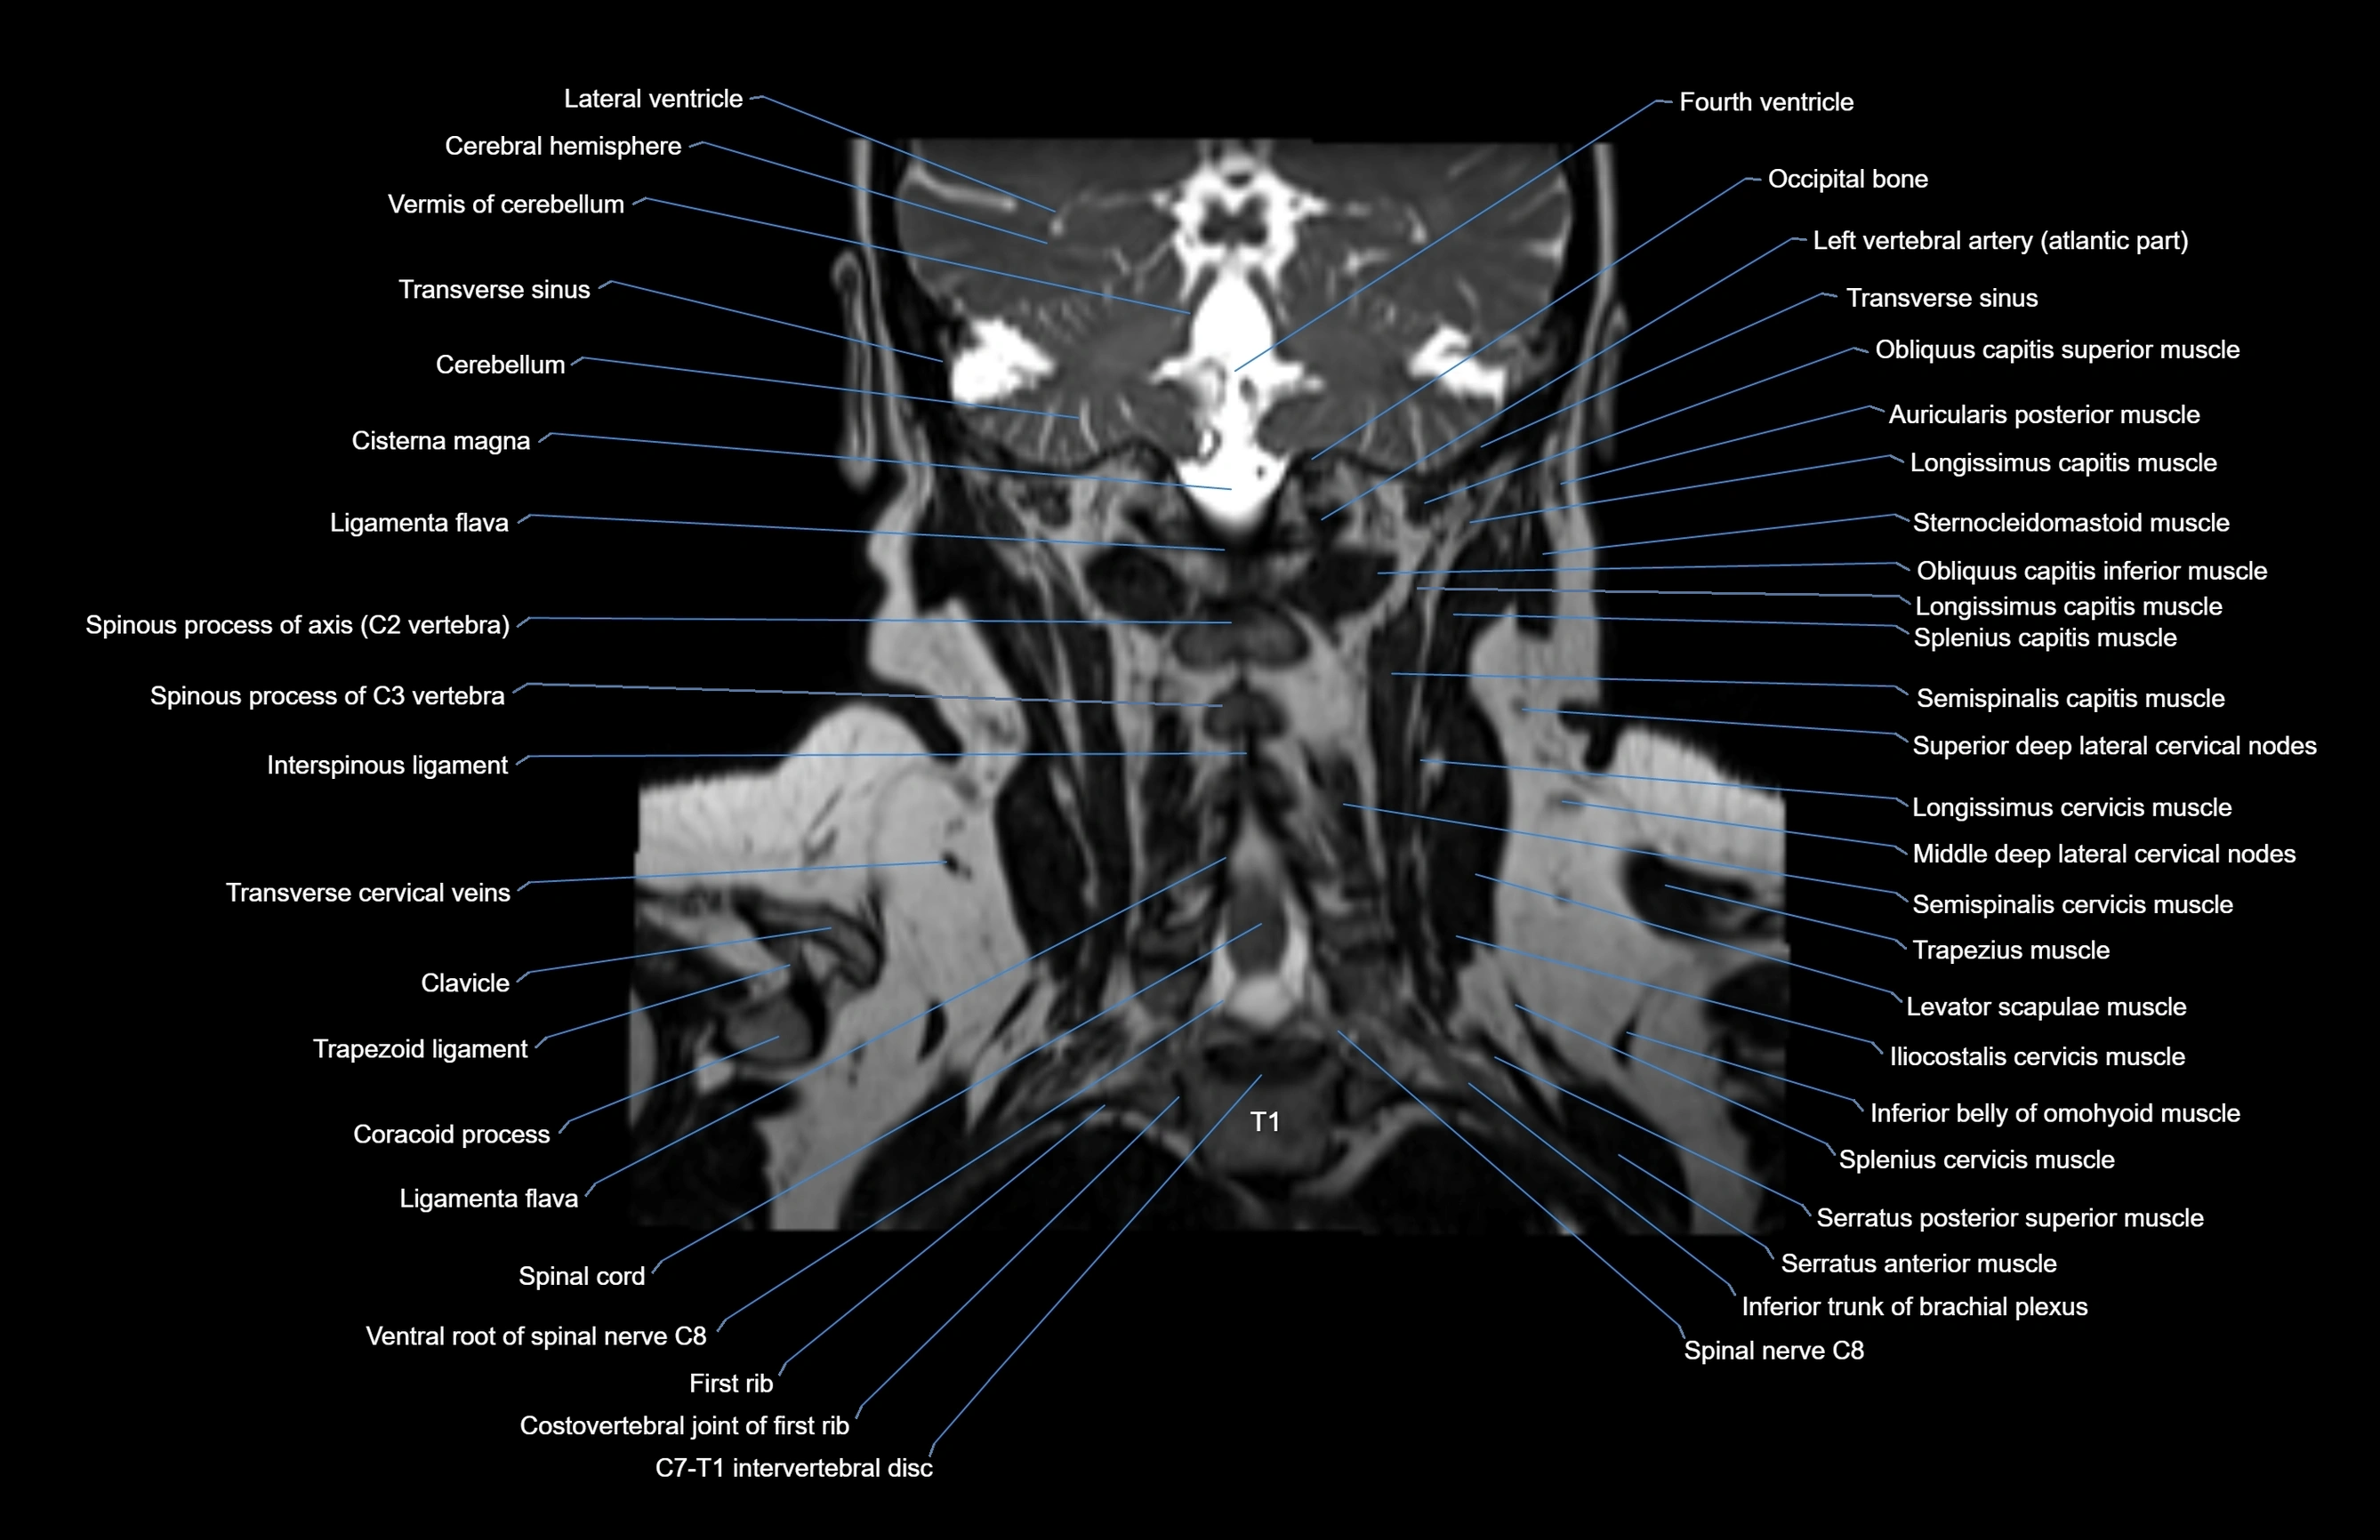

MRI images